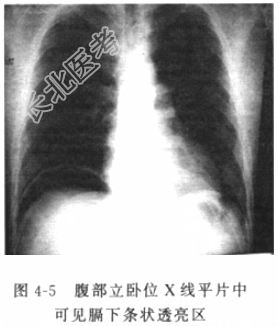

- [材料题] 患者男性,42岁,因“腹胀一周,突发腹痛7h”入院。入院前7天因气温下降受凉后出现“上呼吸道感染(感冒)”,自服“感冒灵”和“阿奇霉素”,服药后自觉“感冒一症状有所好转,但开始出现腹胀伴乏力、不适、食欲下降,稍有恶心,但无呕吐、腹泻和便秘等,上述症状持续约一周。中午在家人劝说下进食了一碗骨头汤,但于下午15时起突然出现严重腹痛,不能忍受,伴恶心、呕吐,经数小时不仅耒见腹痛减轻,反而感到较莆加重,遂于今晚22时急诊我院。本次腹痛发作以来解过一次小便,量不多,呈色黄,无肛门排便及排气。既往有“慢性结肠炎”病史多年,否认其他疾病或手术史。体格检查体温(T)37.8℃,呼吸(R)22次/分,脉搏(P)82次/分,血压(BP)145/85mmHg。神志清楚,查体合作,发育正常,营养中等。皮肤、巩膜无黄染。未扪及浅表淋巴结肿大。颈无抵抗,气管居中,胸廓无畸形,两侧对称,双肺未闻及干、湿啰音,胸膜摩擦音(-)。心律整齐,心浊音界不大,各瓣膜区未听到杂音和心包摩擦音。脊柱、四肢基本正常,未引出病理反射。腹部视诊腹式呼吸消失,腹壁轻度膨隆,未见明显胃肠型及蠕动波。肠鸣音消失,肝浊音界缩小。右侧腹部压痛反跳痛明显,肌紧张。直肠指检未及明显占位,退出时指套无染血。辅助检查血常规示白细胞(WBC)12.8×10⁹/L,中性粒细胞81%,其他实验室检验结果包括肝肾功能、电解质、血气分析结果未见明显异常。腹部立卧位X线平片(图4-5):右膈下见条状透亮区,右膈运动稍弱。腹部CT(图4-6)见小肠管扩张,小肠气液平,可见回盲部占位并套叠。